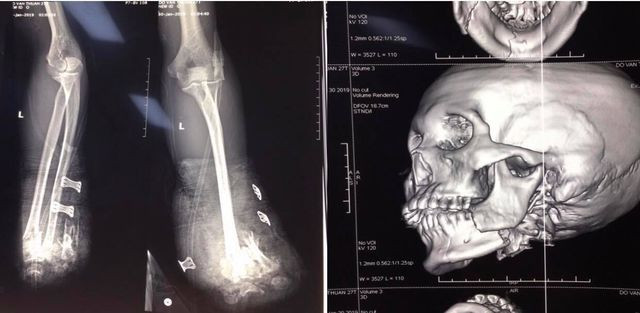

Nam thanh niên bị cụt hai tay, gãy xương hàm vì tự chế pháo nổ ảnh 1Hình ảnh X-quang về thương tích của nạn nhân

Bệnh nhân được chuyển đến khoa Cấp cứu, Bệnh viện Trung ương Quân đội 108 trong tình trạng cụt bàn tay 2 bên, gãy hở xương hàm dưới, chấn thương ngực kín, dập nhu mô thùy trên hai phổi, bỏng rộng vùng ngực, nhiều vết thương nhỏ ở 2 chân.

Bệnh nhân đã được mổ cấp cứu cắt cụt để ngỏ 1/3 giữa cẳng tay phải, cắt lọc cơ dập nát cẳng tay trái, kết xương hàm dưới. Sau mổ, bệnh nhân phải điều trị tiếp tại khoa Hồi sức tích cực của bệnh viện.